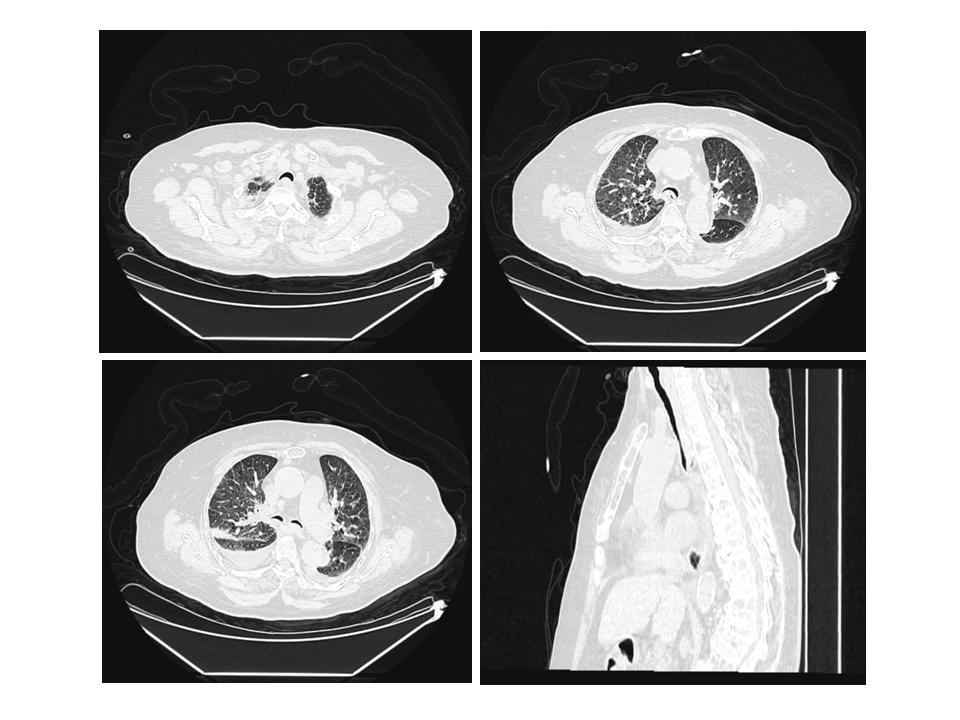

第一次就诊(2020年12月24日):因“阵发性胸闷气促2个月余,加重2 h”呼叫120送来本院就诊。患者近2个月内胸闷气促反复发作,活动后加剧。120到达现场时患者症状已好转。查体:神志清,血压165/92 mmHg(1 mmHg=0.133 kPa),脉搏血氧饱和度93%,呼吸23次/min。肥胖体型,面色无发绀,双肺呼吸音减低,未闻及干湿啰音及哮鸣音。心率110次/min,律规整。急查血常规:白细胞7.77×109/L,中性粒细胞百分比65.6%,床边肌钙蛋白Ⅰ 0.01 ng/mL,高敏肌钙蛋白T 20.4 pg/mL,血钾3.9 mmol/L,血钠132.6 mmol/L,血肌酐89 μ mol/L,血糖7.6 mmol/L。血气分析:pH 7.382,PaO2 68 mmHg,PaCO2 55 mmHg。心电图示:窦性心律,偶发室早。胸部CT平扫(图 1)示:(1)气管、主支气管及其分支退变,气管及双侧主支气管塌陷;(2)双肺慢性支气管炎,双肺多发间质性炎症,双侧胸腔少量积液;(3)左肺上叶前段实性结节,增殖灶可能。右肺上叶尖段及左肺下叶外基底段钙化灶;(4)纵隔及右肺门数枚淋巴结,部分增大。考虑慢性阻塞性肺疾病急性加重期,给予布地奈德雾化吸入、抗感染、平喘对症处理。8 h后患者症状缓解,自行出院。

| 气管及左右主支气管横截面呈新月型改变,膜部向管腔内凸出,气管下段管腔狭窄 > 50% 图 1 患者首次就诊(2020-12-24)胸部CT平扫及三维重建图 |